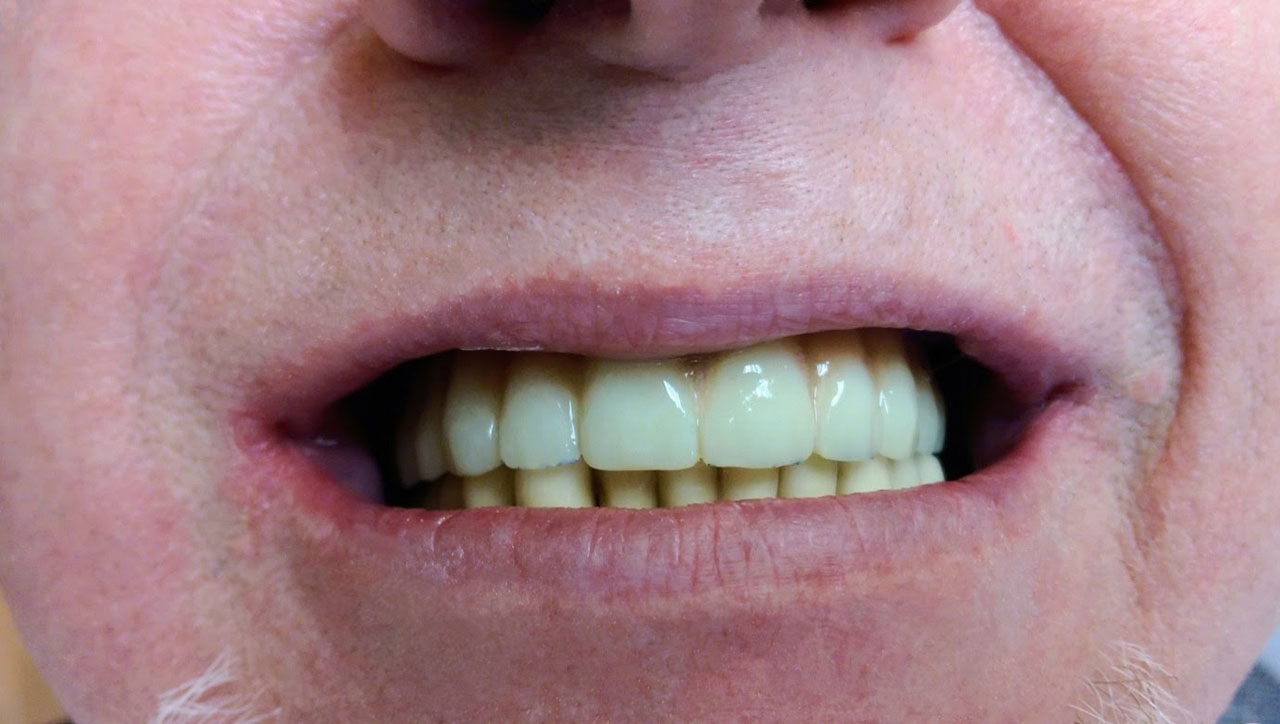

Gyors, biztonságos, kevesebb fájdalommal jár, továbbá kedvező ár-érték arányú! Így jellemezhetnénk legjobban az Ihde Azonnal Terhelhető Implantátumokat, ami már önmagában elég ahhoz, hogy világszerte több mint 100000 páciens választotta a 21. századi orvostudomány egyik legmodernebb fogpótló eljárását.

Sikerét mindenekelőtt a gyorsaságának köszönheti, hiszen a mai rohanó világban kinek van ideje, kedve fogatlanul otthon ülni heteket, hónapokat a fogpótlásra várva? Az Ihde implantációs eljárás során a páciens azonnal, de legkésőbb 72 óra múlva egy rögzített (tehát nem mozgó, nem kivehető) pótlással hagyja el a rendelőt. Ez az egyedülállóan gyors eljárás annak köszönhető, hogy azonnal tudunk implantálni szinte bárhova, akár foghúzás után is, továbbá a művelet nem jár nagy feltárásokkal, nincs szükség csontbeültetésre, így a gyógyulás folyamata is nagyon gyors és a beültetés technikájának köszönhetően maximum 72 óra múlva a korona is feltehető. Tehát ennyi idő alatt foga lesz a betegnek és az implantátum azonnal terhelhetővé is válik.